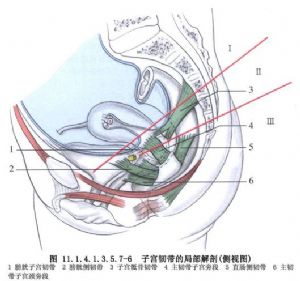

11.6 6.剪開闊韌帶後葉

於子宮骶骨韌帶水平剪開闊韌帶後時,下推直腸達宮外口(圖11.1.4.1.3.5.7-15)。

11.8 8.處理子宮骶骨韌帶、主韌帶,切除子宮